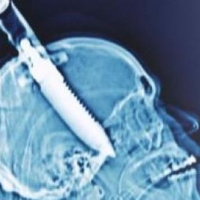

Мужчина 18 лет жил с ножом в голове

Причиной сильных головных болей у жите...